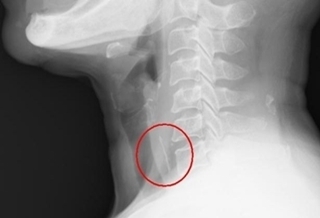

(優活健康往記者徐平/綜合報導)魚刺卡喉怎麼辦?4大撇步快記起來!一位王姓婦人與親友聚餐時邊吃邊聊,沒想到在吞下一塊大魚肉後,覺得有異物卡在了咽喉部,吞了幾口飯、喝了幾口水後情況反更加惡化,經喉纖維內視鏡檢查及頸部影像學檢查,竟發現卡住的大魚骨離血管相當接近,醫師將病人全身麻醉後,開刀將異物取出。不要大口吞飯 先禁食再求診奇美醫學中心耳鼻喉科部主治醫師劉璟鋒表示,這支魚骨很大且呈三角形,相當銳利,離大血管最近處也僅2公分,幸好及時夾出,否則時間一久,一旦穿出食道,後果不堪設想。食用帶骨的食物包含魚,家禽 或豬牛時,務必細嚼慢嚥,如果民眾發生魚刺卡喉的情況,大口吞飯或喝醋可能將魚刺推得更深,反而會造成更大的傷害。最好的處置是先禁食,然後到醫院求診,大部分的情況都可以由醫師將異物夾出,這樣才不會演變成最壞的情況。魚刺或異物鯁到 4建議事項注意奇美醫學中心耳鼻喉科部主治醫師劉璟鋒提醒,如果咽喉太敏感、不容易配合或是異物卡住太深,則有可能需全身麻醉,以硬式喉直達鏡取出,當異物已跑到食道內則可能要以腸胃科的胃鏡或全身麻醉以硬式食道鏡進入食道取出魚刺,當民眾發生魚刺或異物鯁到的情況,有下列幾點需注意的建議事項:1) 勿催吐/勿以手指伸入喉嚨催吐,會讓魚刺刺破的傷口擴大,反而更痛。2) 勿吞飯/因為吞嚥或是食物的推動,會使魚刺由高處往較深的地方移動,而卡到下咽腔或是食道。甚至,有一部份的人吞入的魚刺會進入到胃腸道,讓魚刺從咽喉掉進食道,刺得更深。3) 勿喝醋/喝醋容易造成咽喉黏膜發炎 ,造成二次傷害並延誤就醫,病人喝醋非但沒有化掉魚刺反而造成咽喉黏膜廣泛性的發炎,更不舒服。4) 求助專業/當喉頭出現吞嚥疼痛或不適,應盡速至耳鼻喉科就醫或到大醫院求診。